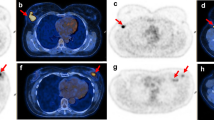

In the patient with a multifocal tumor, two areas of focal uptake on PET images were separately segmented and considered as two different lesions. Results in respect of the features extracted are provided in supplementary Table 3. Collectively, all textural features (i.e., n = 43) were available in 71/79 cases. In 8/79 patients, lesions were smaller than 64 voxels; hence, only first-order parameters were extracted. Figure 1 provides images of two patients as representative examples.

Representative PET/CT images of a patient with pCR (a) and a patient with pathological residual disease (b) after NAC. a A three-dimensional reconstruction of PET/CT images, axial PET — zoom on the primary breast lesion, fused axial PET/CT, and a transverse view of a three-dimensional reconstruction of PET/CT images (panels a, b, c, and d respectively) in an 81-year-old patient with HER2+ breast cancer, estrogen receptor expression 0%, progesterone receptor expression 0%, Ki67 40%, and HER2/neu +++, with no evidence of residual disease at postsurgical histological analysis after neoadjuvant treatment (12 cycles of paclitaxel/trastuzumab). PET parameters (↑ and ↓: above and below the median value): SUVmaximum 14.3↑, total lesion glycolysis (TLG) 33.5↓, CorrelationGLCM 0.52↑, CoarsenessNGLDM 0.035↑, GLNUGLZLM 4.056↓. b A three-dimensional reconstruction of PET/CT images, axial PET — zoom on the primary breast lesion, fused axial PET/CT, and a transverse view of a three-dimensional reconstruction of PET/CT images (panels a, b, c, and d respectively) in a 37-year-old patient with HER2+ breast cancer, estrogen receptor expression 95%, progesterone receptor expression 90%, Ki67 50%, and HER2/neu +++, with persistence of disease at postsurgical histological analysis after neoadiuvant treatment (four cycles of doxorubicin/cyclophosphamide followed by four cycles of docetaxel/trastuzumab). PET parameters: SUVmaximum 19.2↑, TLG 17.8↓, CorrelationGLCM 0.295↓, CoarsenessNGLDM 0.041↑, GLNUGLZLM 2.139↓